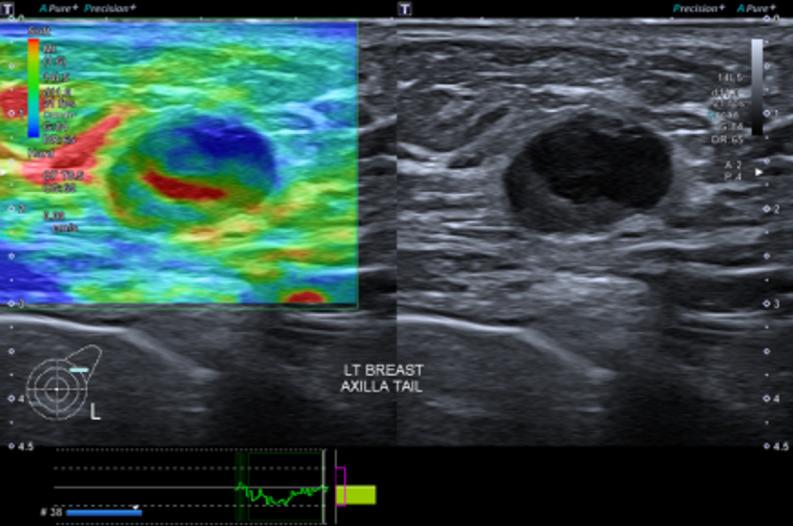

Several new ultrasound tools have been developed to further evaluate breast lesions detected on B-mode ultrasound. Strain elastography (SRE) was developed to assess the likelihood of malignancy of lesions based on their stiffness. This has been incorporated into the latest edition of the American College of Radiology (ACR) Breast Imaging Reporting and Data System (BI-RADS) lexicon and atlas. However, no agreed cut-off stiffness values have been established to distinguish benign from malignant lesions making the translation into routine clinical practice difficult. Superb microvascular imaging (SMI) was developed to better evaluate the vascularity within sonographic lesions and assess their likelihood of malignancy. However, there is also no agreed cut-off value for vascular index (VI) to distinguish between benign and malignant lesions. MicroPure was developed to better visualize and evaluate calcifications seen on ultrasound. Its effective use in breast screening and evaluating the calcifications detected for likelihood of malignancy have not been established. This article describes the original intended uses of these applications and reviews the studies evaluating them, showing the varying success of the translation of these tools into routine clinical practice. Also described are some other uses of these tools for which they were not originally intended. This illustrates the importance of being perceptive to alternative uses of imaging tools in their translation from bench to bedside.

已经开发了几种新的超声工具,以进一步评估在B型超声检查中发现的乳腺病变。应变弹性成像(SRE)是为了根据病变的硬度评估其恶性可能性而开发的。这已被纳入美国放射学会(ACR)乳腺影像报告和数据系统(BI-RADS)词汇表和图谱的最新版本。然而,尚未确定用于区分良性和恶性病变的一致的硬度临界值,这使得其难以转化为常规临床实践。超级微血管成像(SMI)是为了更好地评估超声病变内的血管情况并评估其恶性可能性而开发的。然而,对于区分良性和恶性病变的血管指数(VI)也没有一致的临界值。MicroPure是为了更好地显示和评估超声所见的钙化而开发的。其在乳腺筛查中的有效应用以及评估检测到的钙化的恶性可能性尚未得到证实。本文描述了这些应用的最初预期用途,并回顾了评估它们的研究,展示了这些工具转化为常规临床实践的不同成功程度。还描述了这些工具的一些并非最初预期的其他用途。这说明了在成像工具从实验室到临床的转化过程中,敏锐地感知其替代用途的重要性。